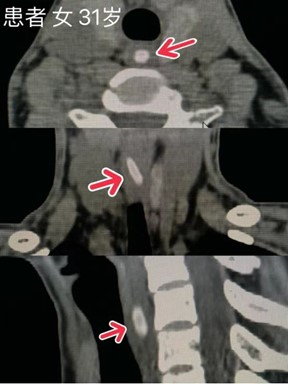

非金属异物或透光异物应建议进行CT检查(如鱼刺、枣核、鸡骨头等),可直观了解有无异物,异物的位置、大小、形态及毗邻关系,并可通过后处理技术进一步了解异物具体情况,还可进一步评估异物周围组织损伤的程度。如异物滞留体内时间较长,尤其食管异物,在行异物取出术前应行CT检查,当怀疑异物合并腹膜炎、脓肿、瘘管、食管异物穿孔等需要外科手术干预时,可行CT检查。需要注意的是,即便完善胸腹部CT检查,可能由于胃肠内容物等原因,少部分的消化道异物仍无法明确诊断。

食管颈段异物(枣核)

异物(枣核)自行掉入胃腔内